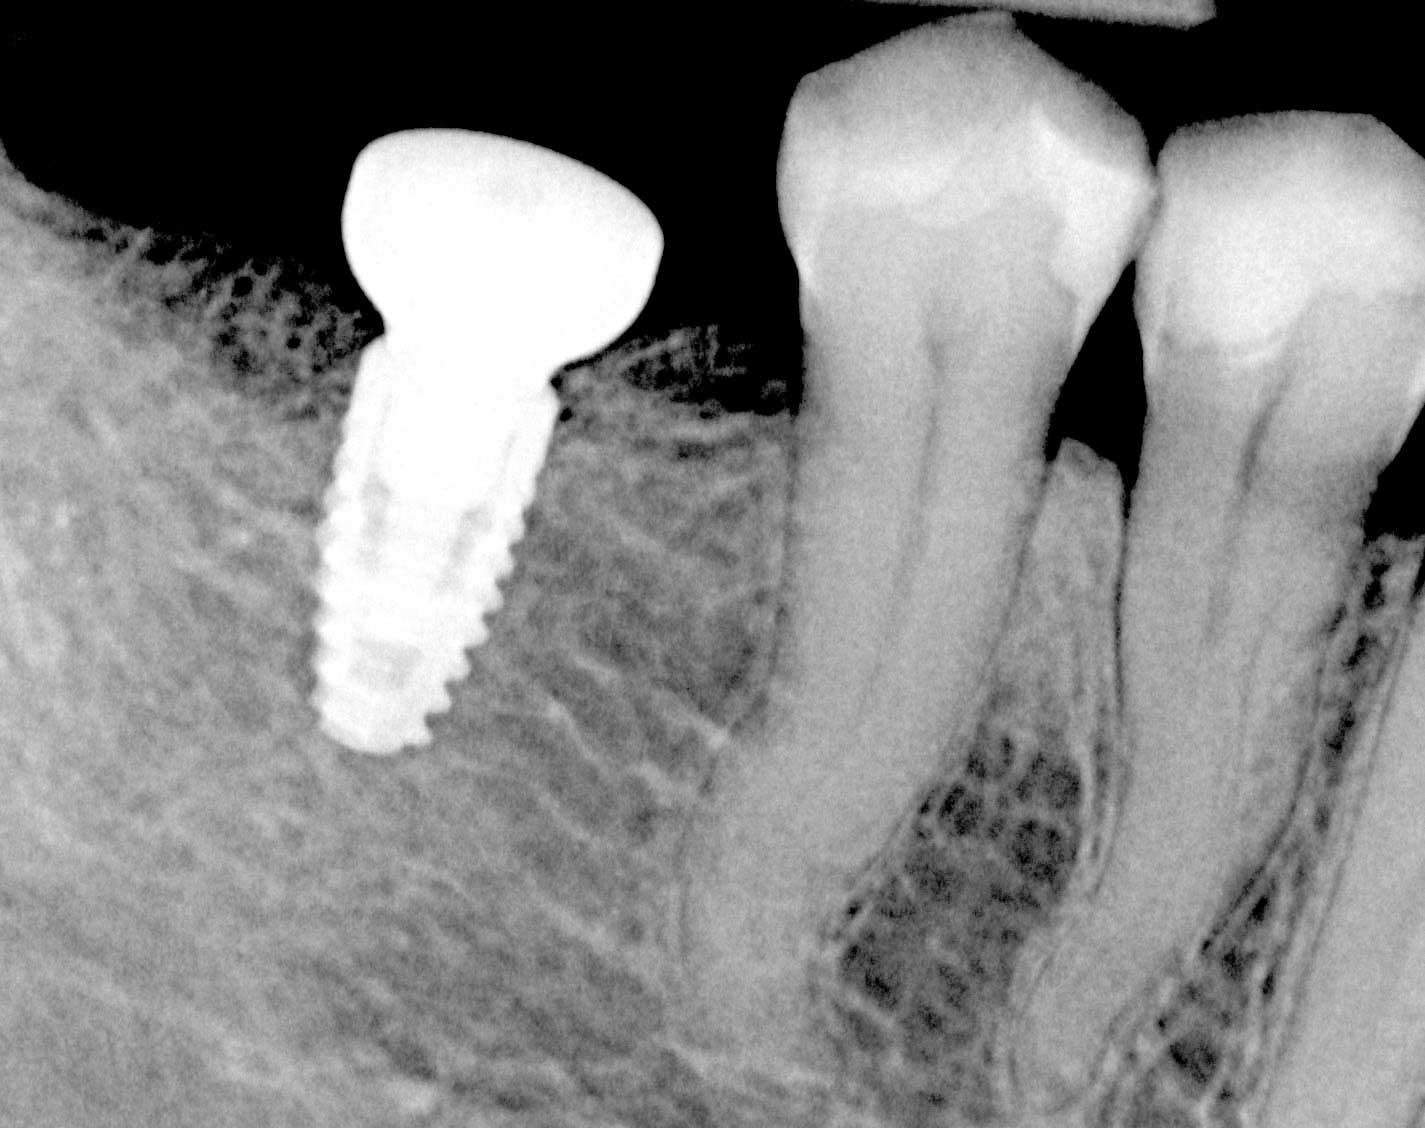

Initial x-ray showing bone loss around implants placed 5 years ago in another dental clinic